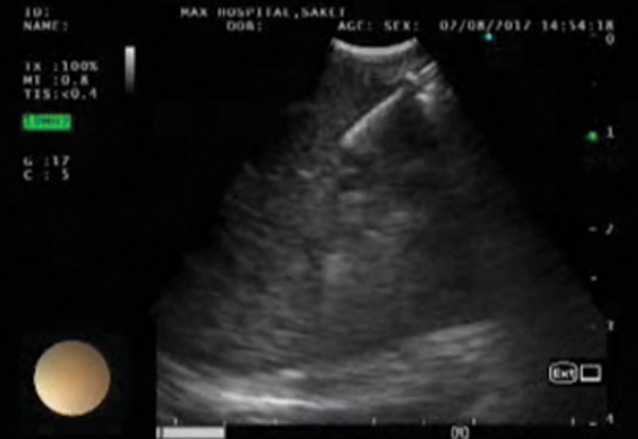

Fibreoptic bronchoscopy was performed, which was normal with no endobronchial growth. EBUS-TBNA was performed from nodal stations 4R (lower right paratracheal lymph node), 7 (subcarinal lymph node), 10R and 10L (right and left hilar lymph nodes), and from the left lower lobe mass lesion (figure 2). Rapid on-site evaluation was done to check for adequacy of samples. An aspirate was obtained from the left lower lobe mass lesion using sustained suction by syringe during the puncture by the TBNA needle. This sample was sent as a cell block after squirting the aspirate on filter paper and then placing it into 10% formalin for subsequent processing in the laboratory. The final histopathology was suggestive of nonsmall cell carcinoma. Among the lymph node stations that were sampled, the subcarinal lymph node was positive for malignant cells and rest were suggestive of reactive lymph nodes.

Figure 2.

EBUS-TBNA from the left lower lobe mass.